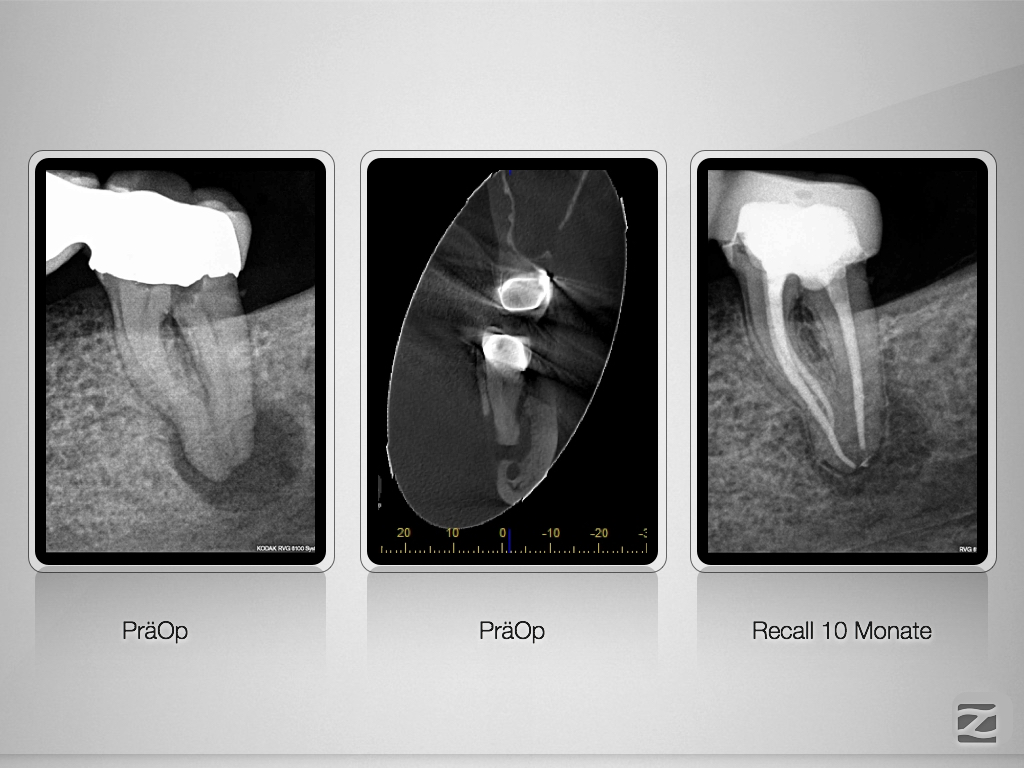

Recall einer ausgedehnten apikalen Lyse